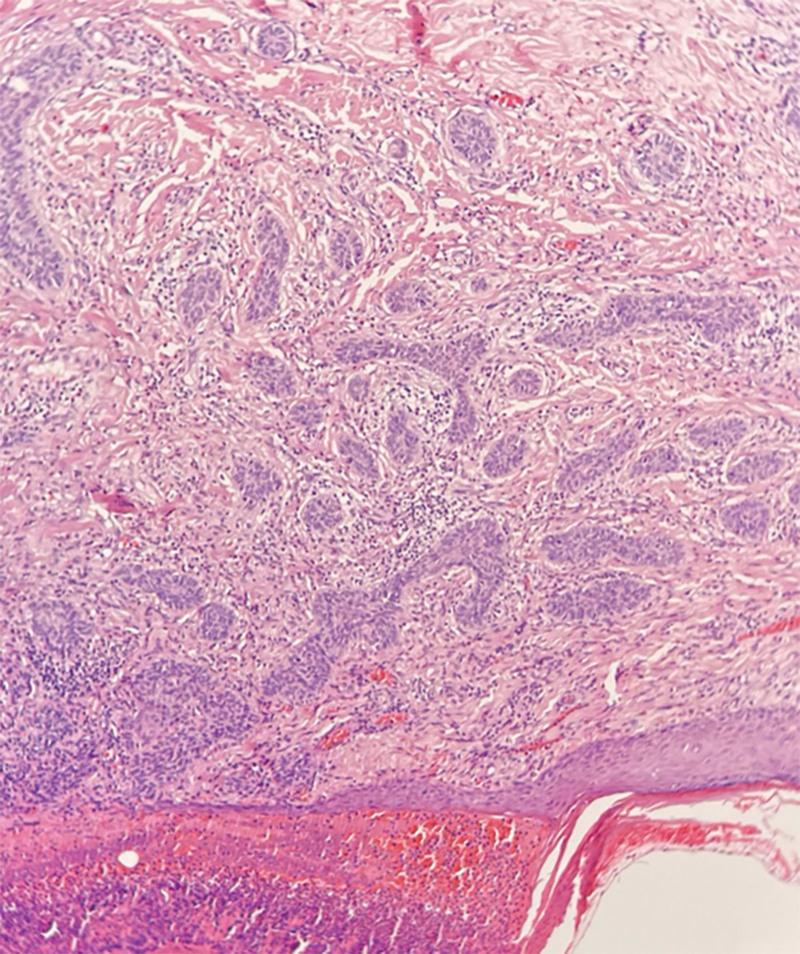

This report describes a recurrent sclerodermiform basal cell epithelioma of the malar region next to the inferior eyelid in a 57-year-old woman. Three interventions were necessary to obtain a clear margin of resection. The area of resection was closed with a local cutaneous flap. We report a rare basal cell carcinoma subtype underestimated in its aggressiveness with often inadequate medical and surgical management. This tumor, generally localized in the face, often requires aggressive surgery, and aesthetic results can be poor. The patients require close long-term follow-up even when margins are clear. General practitioners, dermatologists, and surgeons should be aware of sclerodermiform basal cell carcinoma, which is a malignant, aggressive, and recurrent tumor.

本报告描述了一名57岁女性下眼睑旁颧部复发性硬皮病样基底细胞上皮瘤。为获得清晰的切除边缘,需要进行三次手术干预。切除区域采用局部皮瓣闭合。我们报告了一种罕见的基底细胞癌亚型,其侵袭性被低估,医疗和手术管理往往不足。这种肿瘤通常位于面部,常需要积极的手术治疗,且美学效果可能较差。即使切缘清晰,患者也需要长期密切随访。全科医生、皮肤科医生和外科医生应了解硬皮病样基底细胞癌,这是一种恶性、侵袭性和复发性肿瘤。